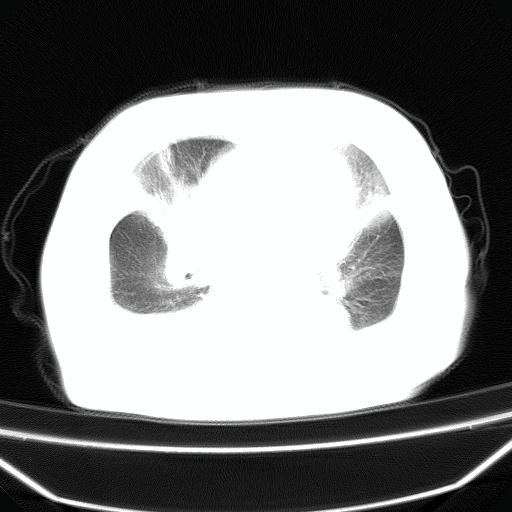

以下是引用jiangjing在2008-4-20 10:43:00的发言:[br]结合病史支持 冠心病[冠状动脉钙化],心功能不全,肺淤血、肺水肿,双侧胸腔与斜裂积液

以下是引用liuyue在2008-4-19 22:25:00的发言:[br]先考虑:1.心衰伴肺水肿、双侧胸腔积液、叶间积液、双下肺不完全性肺不张; [br] 2.冠状动脉粥样硬化。